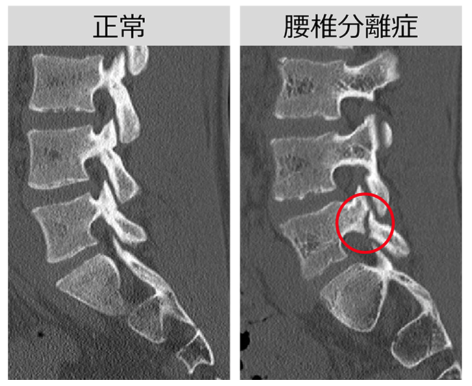

実際に疲労骨折してしまった画像はこちら。正常な左側の画像に比べて、分離症が起こった右の骨には亀裂が走っており、ブロックと羽がまさに“分離”されているのがわかりますね。

(丸田町リハビリテーションクリニックHPより引用)